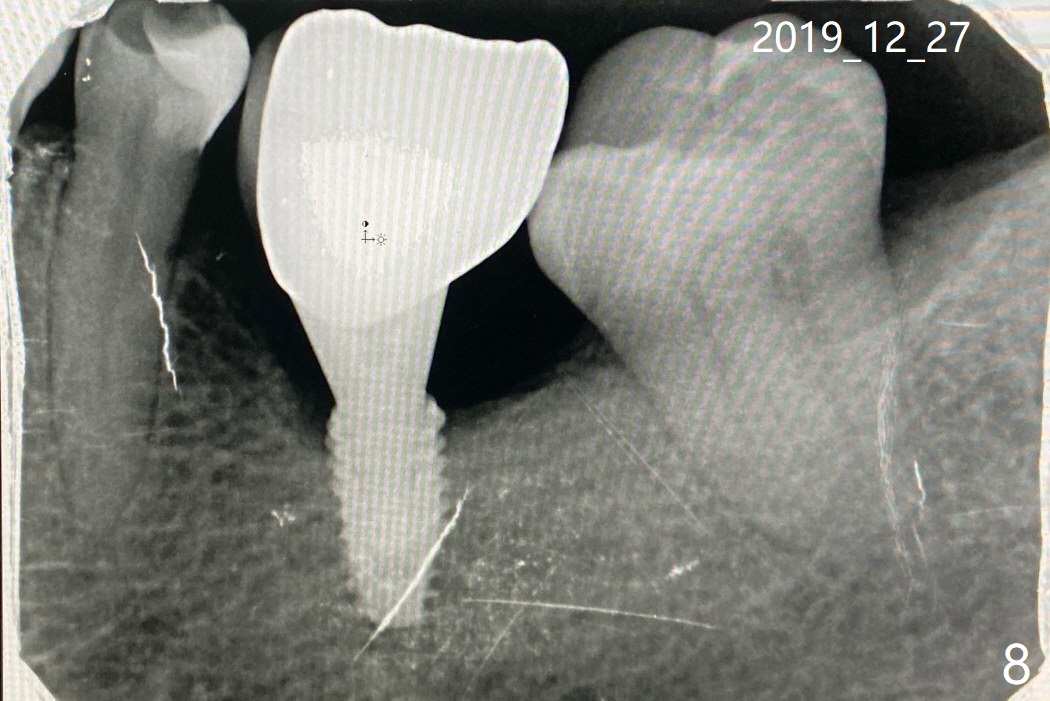

几经周折,植牙修复了。您的工具我会找朋友带回去,或者等我去的时候带给您?如果不急着要的话。谢谢给予的支持!图八 Dec 27 at 7:14 AM

工具不急。最好做左下五和七牙冠,减少植牙负担和松动。现在这两个牙齿咬合不好,咬合面有点歪。另外继续用水牙线,如果右边牙齿不好,也需要及时治疗,争取两侧咀嚼。

没事就行。万一再松,恰好你马上回美国,叫医生放置healing abutment 6 or 6.8x7 mm, 事先涂抗菌素软膏。如果疼痛明显,使用直径小些healing abutment. 如果你们执意放回牙冠,多拍摄一张根尖片,拍摄时尽量与牙齿平行,寄给我,原件。如果能把最后一张根尖片,原件,寄来,更好。

Dec 28 at 8:00 AM